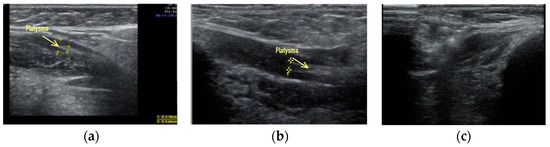

Clinical case #2. During the study, a 52-year-old female patient with a 15 MHz linear transducer of soft tissues of the lower third of the face and neck without pressure, in an upright position, displayed sagging platysma and the presence of cords on two sides (Figure 2a,b) as well as a slight accumulation of adipose tissue in the chin area (Figure 2c).

B-mode ultrasound examination of the soft tissues of the lower third of the face and neck with a 14 MHz linear transducer. Sagging of the platysma, strands (a,b), and a slight accumulation of adipose tissue in the submental area (c).

According to the results of ultrasound examination, it is obvious that a radical improvement in the contours of the neck–submandibular angle will not be achieved by acting only on the adipose tissue; correction of ptotic platysma is also necessary in this clinical case.